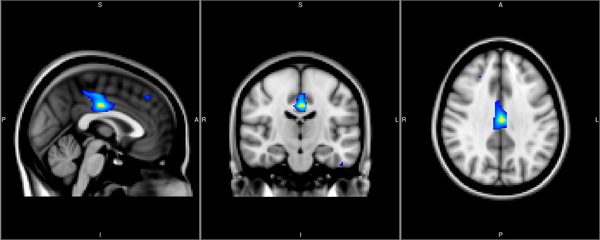

研究表明,绝大多数精神疾病易感基因均可以影响脑结构的变化,而这种效应无论是在病人中还是健康人群中均存在。有鉴于此,中国科学院昆明动物研究所宿兵研究员实验室(李明博士)通过与复旦大学冯建峰教授的实验室合作,对来自昆明的包含278个健康个体的人群进行了脑部结构的核磁共振扫描(MRI),并在全脑范围内分析了rs1545843与脑区结构变化的关系。他们的研究结果发现,rs1545843与大脑中部扣带回体积显著相关(下图)。

众所周知,扣带回在大脑中主要参与情绪以及认知进程,而情绪及认知能力的改变是抑郁症患者的一个主要症状,并且有证据表明扣带回体积在抑郁症患者中发生了明显病变。因此,他们的研究结果进一步支持了SLC6A15基因在抑郁症发病中的作用,并且提示了其可能的致病机制。